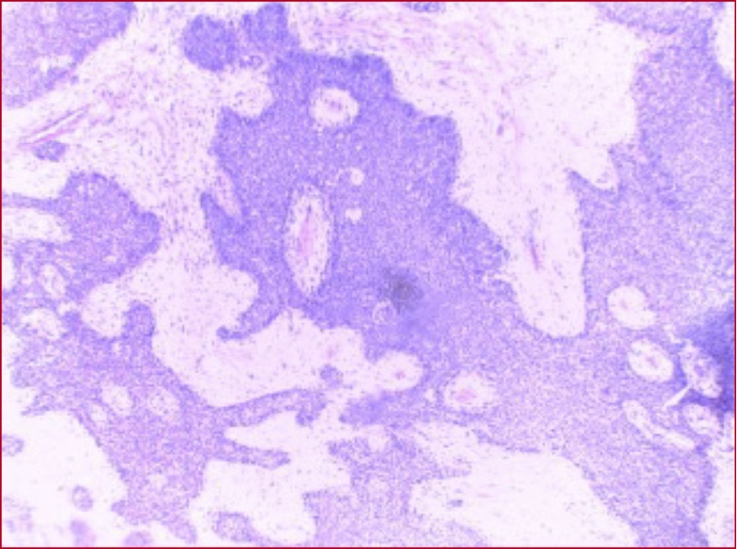

A pesar del esfuerzo multidisciplinario, la paciente falleció debido a un shock resistente e insuficiencia multiorgánica. El resultado de la biopsia, informado semanas después, confirmó la presencia de un carcinoma tímico de células escamosas (Figura 3).

Figura 3. Corte histológico de la biopsia diferida. Se observan fragmentos tisulares compuestos por tejido fibroso y músculo estriado, en los cuales se identifica una proliferación de células escamosas monomorfas con atipia moderada, acompañada de focos de necrosis e infiltrados inflamatorios mixtos.